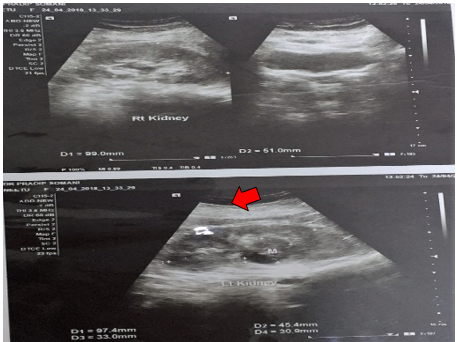

A 40 years old female presented in the Department of Urology with the chief complaint of left flank pain since one year. On USG (W/A), left kidney showed a mixed echogenic lesion measuring 33 x 30.9 mm, involving the mid pole. Figure 1 CECT (W/A) showed evidence of heterogeneous enhancing mass lesion measuring 44 (SI) x 42 (AP) x 35 (TR) mm,

Figure 1: USG (KUB) shows a mixed echogenic lesion measuring 33 x 30.9 mm, involving the mid- pole of the left kidney.

arising from the mid pole of the left kidney with small exophytic component in left perinephric space. Figure 2 No significant lymph nodes were noted.